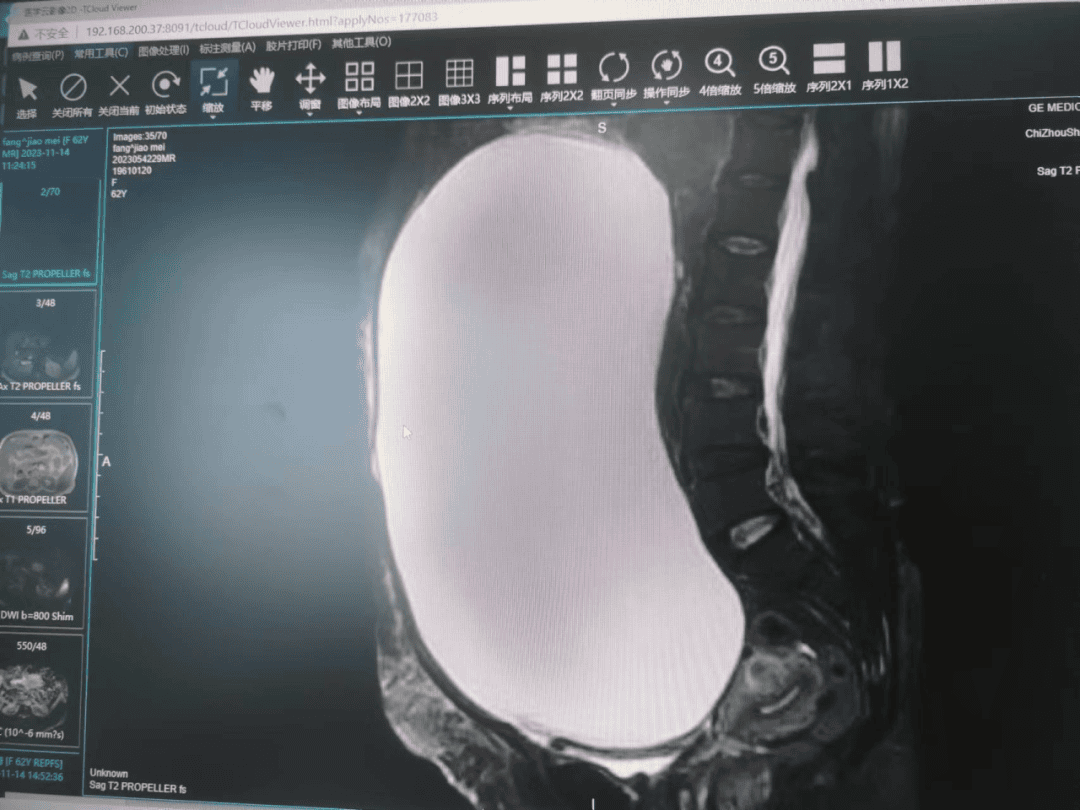

2023年11月14日上午,妇产科冯宝明主任接到外科医生电话:一个62岁老太太因解大小便困难半月就诊,CT提示盆腹腔巨大包块,请妇产科会诊。经查体发现,包块巨大如孕足月大小,从小腹一直到剑突下。为查清包块来源及性质,冯宝明主任立即给病人安排了核磁共振检查,MRI提示包块可能来源于右附件,即将病人转至妇产科进一步诊治。

在周密准备和计划后,11月17日上午,由妇产科冯宝明主任、田丽丽副主任医师率领团队对病人实施剖腹探查术,术中缓慢放液7000ml后探查发现包块来源于右卵巢,左卵巢表面也有异常病灶,均切除后送快速病理结果提示:左卵巢交界性肿瘤,局灶癌变;右侧卵巢交界性肿瘤。病患为卵巢恶性肿瘤,在与家属沟通后立即扩大切口,实施卵巢癌全面分期手术。手术结果非常成功,且患者术后在妇产科全体医护人员的精心照料下康复良好,目前已顺利出院。